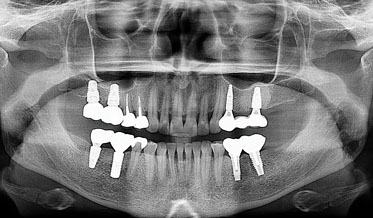

Using Three Familiar Radiographic Shapes to Improve Dental Implant Longevity